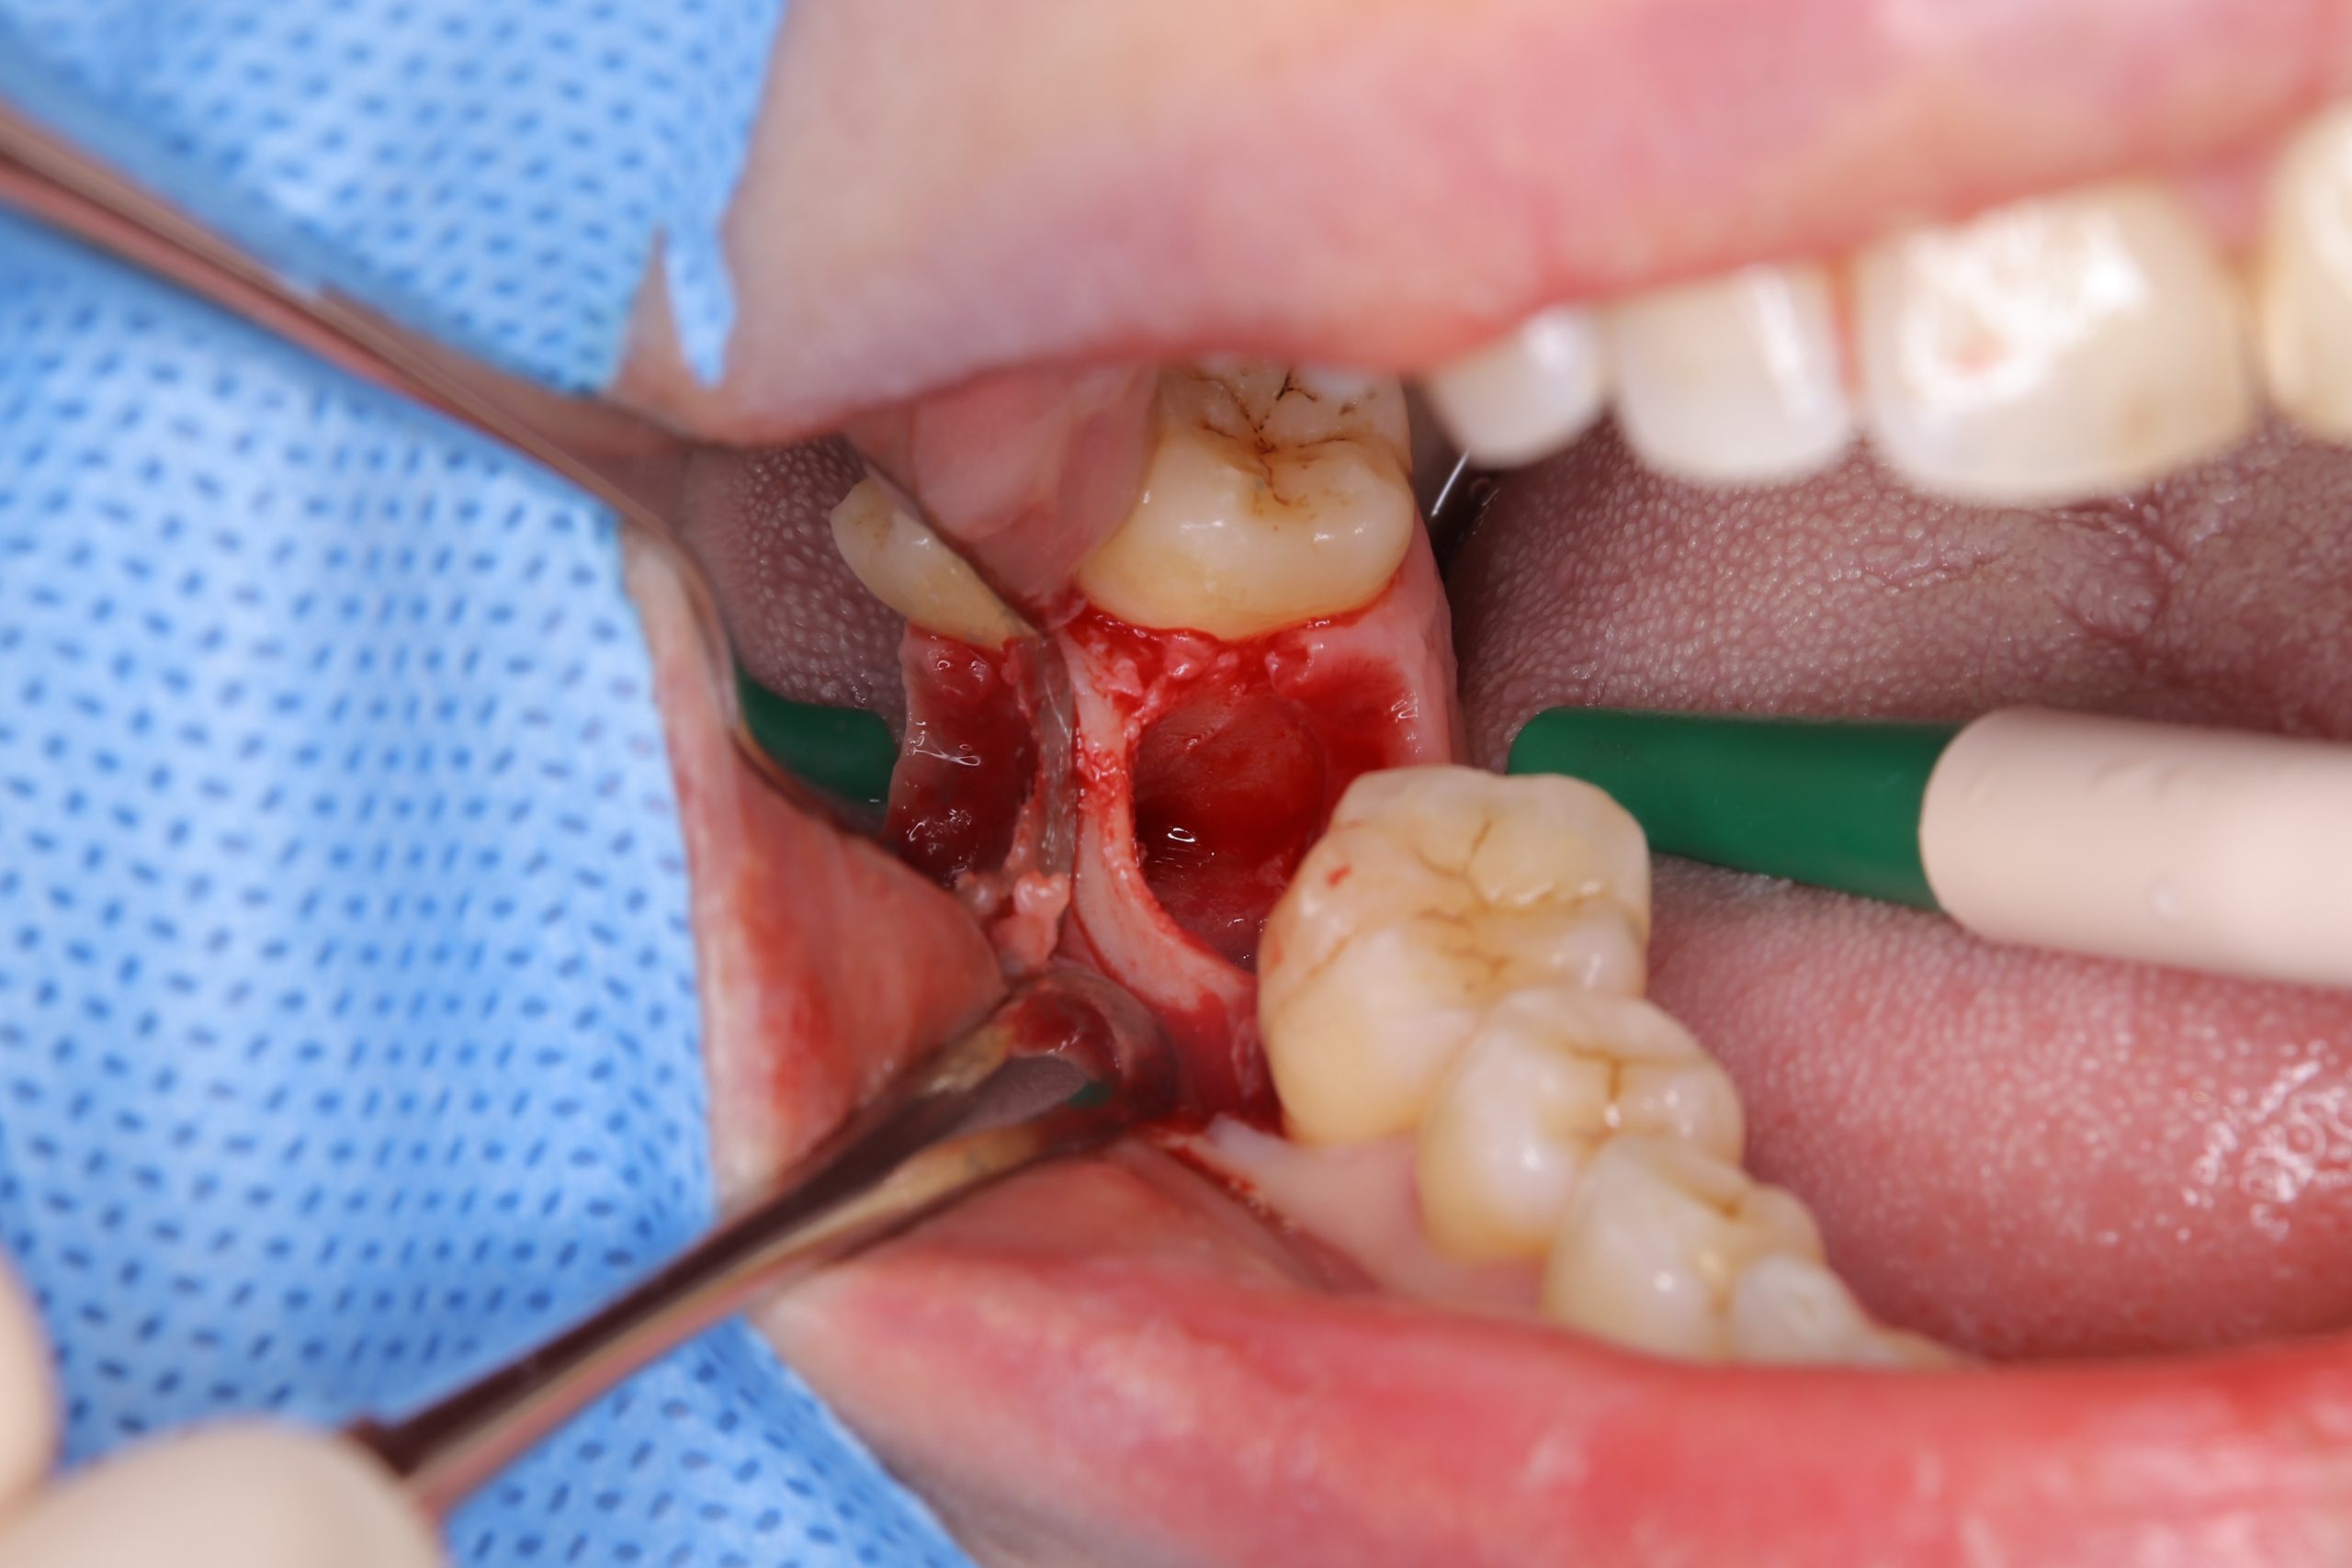

予後不良歯を抜歯し、移植する親知らずが設置できるよう、抜歯窩(抜歯した穴)の形を整えます。

移植歯の形と設置位置を色々考えながら、抜歯窩周囲の骨を削っていきます。

そして、下の写真のように、抜歯した親知らずを移植し、安静を図るため手前の歯と固定しました。